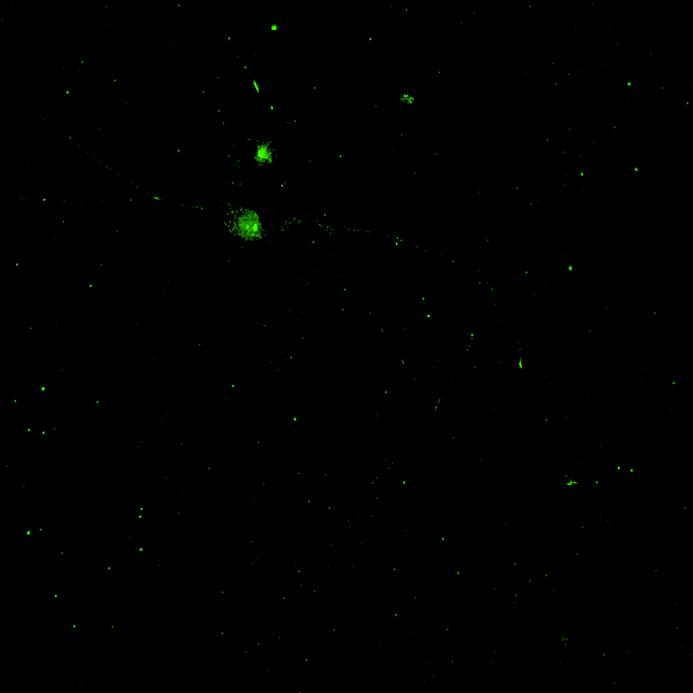

• Isogenic control or SNCA A53T mutation neurons were plated in both chambers of a microfluidics device then cultured to allow the neurons to connect via the microchannels

• PFFs were added to the donor chamber only before fixing and labelling for pS129 α-synuclein

• pS129 positive neurons were detected in donor chambers due to directly applied PFFs and acceptor chambers due to seeded PFFs, though automated analysis failed to detect the small proportion of positive wildtype neurons in acceptor chambers

Projection of neurites through microchannels at 2 weeks

• A53T mutation increases pS129 pathology in both donor and acceptor chambers